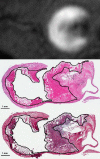

Carotid therosclerotic disease causes approximately 25% of the nearly 690,000 ischemic strokes each year in the United States. Current risk stratification based on percent stenosis does not provide specific information on the actual risk of stroke for most individuals. Prospective randomized studies have found only 10 to 12% of asymptomatic patients will have a symptomatic stroke within 5 years. Measurements of percent stenosis do not determine plaque stability or composition. Reports have concluded that cerebral ischemic events associated with carotid plaque are intimately associated with plaque instability. Analysis of retrospective studies has found that plaque composition is important in risk stratification. Only MRI has the ability to identify and measure the detailed components and morphology of carotid plaque and provides more detailed information than other currently available techniques. MRI can accurately detect carotid hemorrhage, and MRI identified carotid hemorrhage correlates with acute stroke.